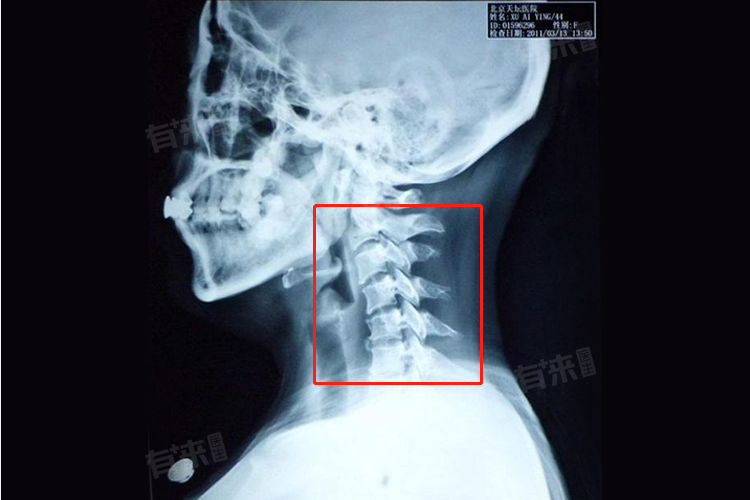

颈椎弧度变直作为颈椎病的一种常见表现,不仅影响着患者的生活质量,还可能引发一系列严重的健康问题,防治措施主要有调整生活习惯、加强锻炼等。

- 颈椎自然状态下呈现出一个向前凸出的生理曲度,对于维持颈椎的稳定性、保护脊髓和神经根免受压迫至关重要。随着现代生活方式的改变,如长时间低头看手机、电脑办公、不正确的坐姿及睡姿等,导致颈部肌肉长时间处于紧张状态,颈椎前凸的生理曲度逐渐减小,甚至反向变直,形成所谓的颈椎弧度变直。